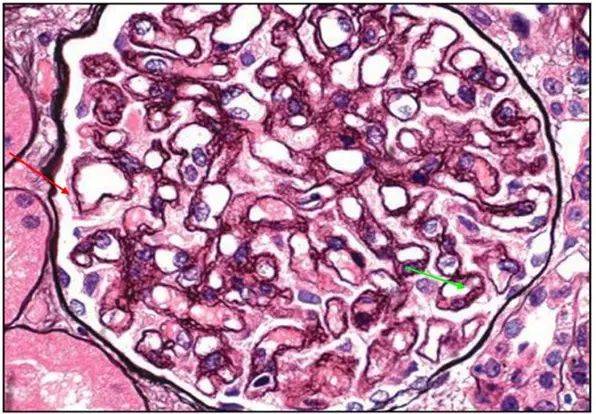

原發(fā)性膜性腎病(membranous nephropathy,MN)又稱膜性腎小球腎炎(membranous glomerulonephritis),病理特點是腎小球基底膜上皮細(xì)胞下彌漫的免疫復(fù)合物沉積伴基底膜彌漫增厚。臨床以腎病綜合征(NS)或無癥狀性蛋白尿為主要表現(xiàn)。